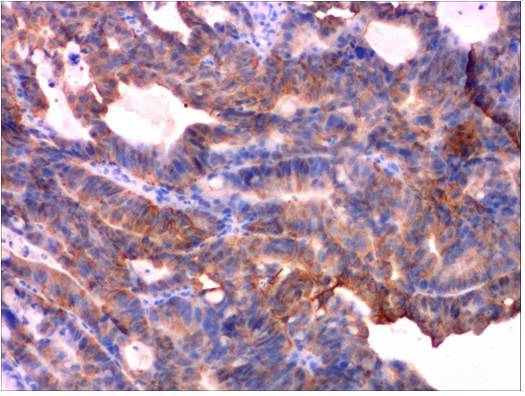

患者于2009年12月18日在当地医院体检行腹部B超检查时发现肝内多发占位性病变,最大者为3.9×3.7cm,腹膜后多个肿大淋巴结,大小为3.4×2.2cm。腹部CT平扫+增强示:肝内可见多发占位性病变,胃小弯侧淋巴结及腹膜后可见多个肿大淋巴结。2009年12月19日就诊于我院行胃镜检查,病理示:胃(底)中-低分化腺癌,累及鳞状上皮粘膜。免疫组化:HER-1(-),HER-2(++),p53(-),Ki-67(+<5%),VEGF(++)。患者偶有上腹部不适,体重无明显变化。为进一步治疗收住我院。

第一次胃活检

第一次胃活检HER-2

胃镜检查(2009-12-19我院):贲门见隆起肿物,延伸至胃底大弯后壁,胃底见边缘隆起凹陷性溃疡。病理示:胃(底)中-低分化腺癌,累及鳞状上皮粘膜。免疫组化:HER-1(-),HER-2(++),p53(-),Ki-67(+<5%),VEGF(++)。